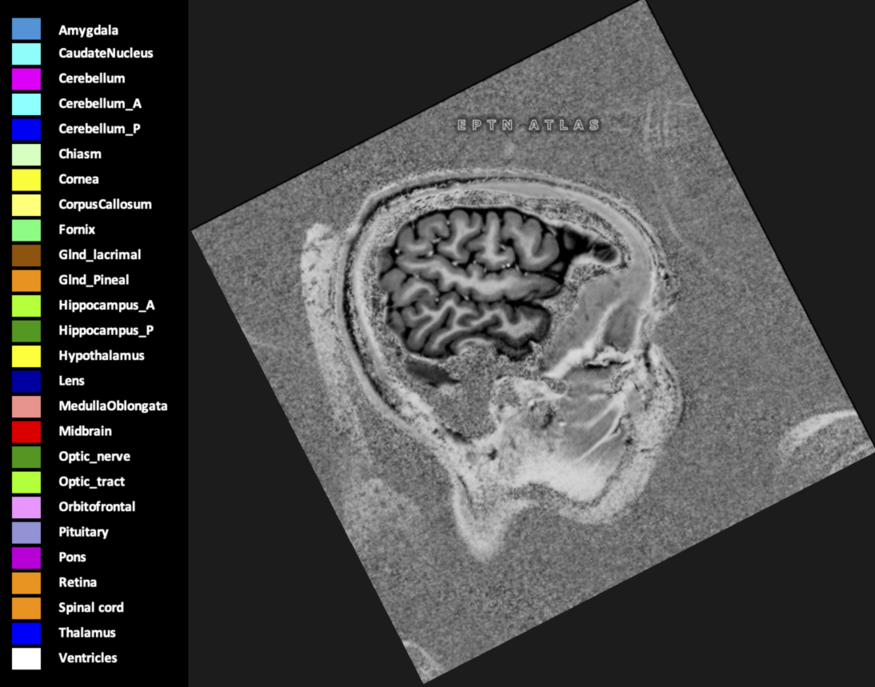

Eekers et al. have published an international neurological atlas for contouring of organs at risk in consensus with the European Particle Therapy Network (EPTN) in 2018 and an update in 2021. The purpose of this consensus atlas is to decrease inter- and intra-observer variability in delineating OARs relevant for neuro-oncology.

Included are all OARs known to be relevant for radiation-induced toxicity in neuro-oncology: brain, brainstem (midbrain, pons, medulla oblongata), chiasm, cerebellum (anterior & posterior), cochlea, cornea, hippocampus (anterior & posterior), hypothalamus, lens, lacrimal gland, optic nerve, pituitary, skin, and vestibular & semicircular canals. To further facilitate research on cognition, vision and radiological changes after irradiation of the brain, potential clinically-relevant OARs are included: amygdala, caudate nucleus, cerebellum (anterior & posterior), corpus callosum, fornix, macula, optic tract, orbitofrontal cortex, periventricular space (PVS), pineal gland, and thalamus.

Three-dimensional delineation of the 25 consensus OARs for neuro-oncology are shown on CT (WW/WL 120/40, 3000/600), 3T MR images, (T1Gd, T2FLAIR 1mm) and 7T MR (MP2RAGE 0.7 mm). All are presented in transversal, sagittal and coronal view.